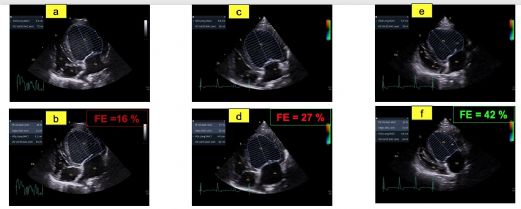

- La valeur très diminuée de la fraction de raccourcissement (FR) égale à 6 %; (valeurs usuelles (VU) 29%) (Figure 1A) ainsi que de la fraction d'éjection (FE) ventriculaire gauche égale à 16% ; (VU 42%) (Figures 2A et 2B) ;

- Une dysfonction systolique nettement améliorée avec une fraction d'éjection normalisée à J0 + 9 mois (Figures 2E et 2F, Tableau 2) malgré la persistance d'une hypokinésie radiale du septum interventriculaire qui contribue au maintien d'une fraction de raccourcissement diminuée mais de façon moindre (FR égale à 23 % à J0 +